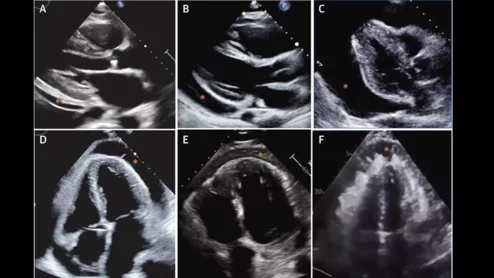

pericarditis cardiac imaging

Pericarditis, inflammation of the pericardium, accounts for approximately 5% of all emergency department evaluations for chest pain. These new recommendations are designed to help guide clinicians through the ins and outs of patient care.